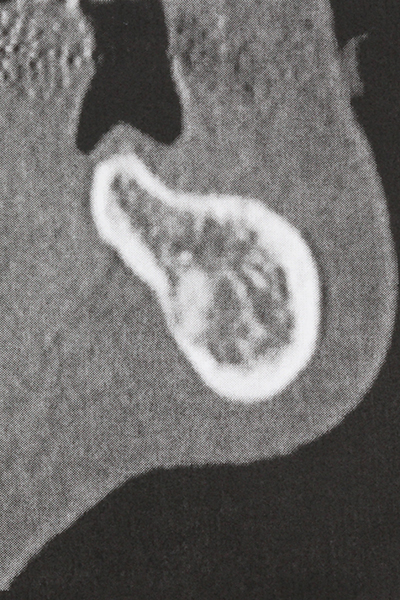

Bone tissue is not simply a mineral structure but also contains a substantial proportion of collagen fibres. This means it not only has good compressive strength but also a degree of flexibility, which can be taken advantage of when performing bone augmentations. In the classical expansion procedure using bone splitting, the atrophied alveolar ridge is split longitudinally and carefully expanded after reaching an adequate osteotomy depth (Fig. 13-16), ideally without substantial removal of the periosteum (Brugnami, Caiazzo et al. 2014, Stricker, Fleiner et al. 2014). Screw and plate systems with increasing expansion distance have proven effective in separating the two bone lamellae while remaining below the fracture threshold. In general, residual bone widths of at least 3–4 mm are required (Chiapasco, Zaniboni et al. 2006) to guarantee adequate flexibility and sufficient bone coverage of the future implants. If necessary, a vertical relief osteotomy on one or both sides can improve flexibility. A combination with additional augmentation techniques, particularly on the buccal side, has been described as an alternative to the classical technique.

The splitting procedure is particularly atraumatic and there is no significant loss of dimension when using piezosaws, and there are no significant differences between implants in split jaws and implants in an alveolar ridge without a bone deficit (Chiapasco, Zaniboni et al. 2006, Danza, Guidi et al. 2009). However, sufficient continuous irrigation is essential, particularly with locally restricted and deep splitting to prevent thermal stress in the apical osteotomy regions.